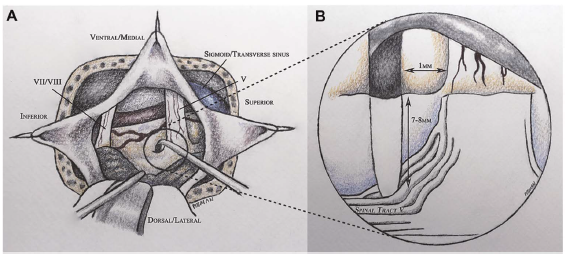

There was no arterial compression of the left trigeminal nerve shown on a brain MRI with diffusion tensor imaging (DTI) sequences. The decision was made to take her to surgery for a left-sided microvascular decompression (MVD) and possible tractotomy via a retrosigmoid approach. At surgery, a compressing vein over the dorsum of the left trigeminal nerve was noted and dissected off the nerve; a muscle graft was gently wedged in place to separate the vein from the nerve. No convincing arterial compression was found. A tractotomy of the descending nucleus of the trigeminal nerve was performed using stereotactic neuronavigation and microscopic visualization of the inferior aspect of the trigeminal nerve root entry zone; the preferred entry point for the VPT procedure is 1mm inferolateral to this point (Figure 1).

Low power micro-bipolar electrocautery is used to incise the pia and a 6-8 mm right-angled microdissector (tracked by the neuronavigation system) is used to enter into the brainstem to a depth of 7-9 mm in a plane parallel to the trigeminal nerve proceeding dorsomedially to the descending spinal tract of the trigeminal nerve (Figure 1). Neuronavigation is used to guide the microdissector 2-3 mm along the inferior aspect of the pontine descending trigeminal pathway. This action facilitates the disruption of the spinal tract of the trigeminal nerve superior to the point at which it converges into a vertical compact tract (Figures 1 and 2). The anterolateral corner of the rhomboid fossa and fourth ventricular floor plane is used to guide the trajectory of the microdissector (Figure 2).